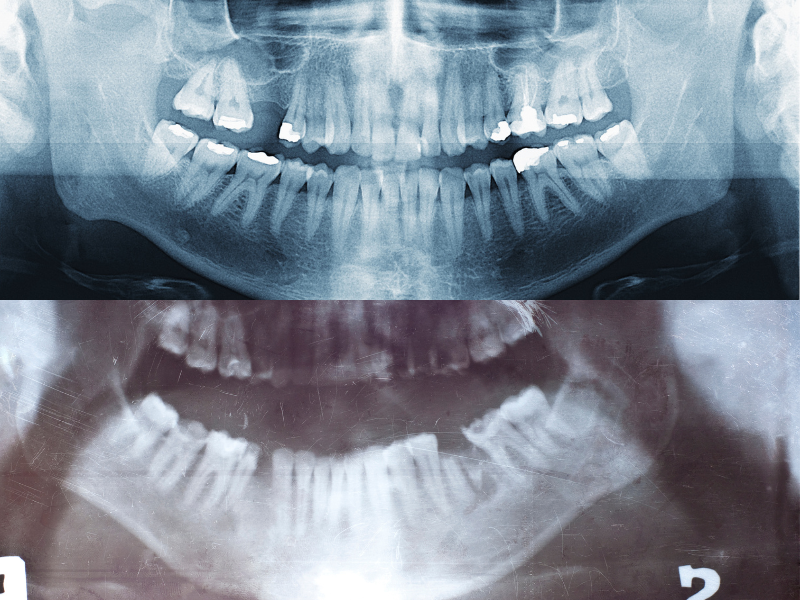

Root Canal Treatment, often referred to as endodontic therapy, is a procedure designed to save a tooth that is badly infected or decayed. At our practice, we understand that the thought of a root canal might make you anxious, but rest assured, this treatment is not only effective but also virtually painless with modern techniques.

Wisdom teeth, or third molars, are the last set of teeth to develop, typically emerging in the late teens or early twenties. While some people’s wisdom teeth come in without any issues, others may experience pain, crowding, or other complications that require removal. At our practice, we specialize in wisdom teeth surgeries, providing safe and effective treatment to protect your oral health and relieve discomfort.